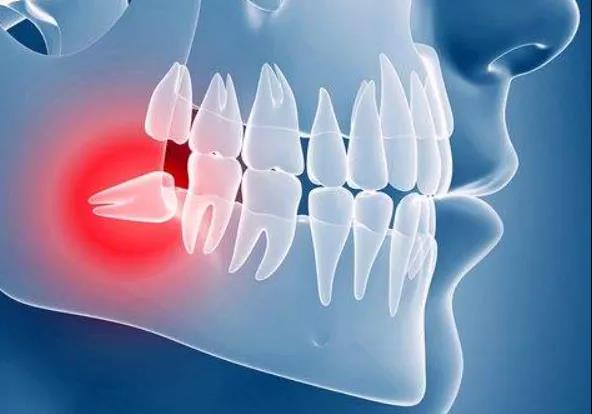

反之,智齿萌发空间不足就会形成阻生智齿,那么它会有什么影响呢?首先,它会引起牙口不齐,冠周间隙感染,张口疼痛,对人的身心健康影响较大。

其次,大多数的智齿是前倾阻生的,会与第二磨牙形成45度的牙冠尖角,容易嵌塞食物,时间久了导致第二磨牙龋坏,严重时会出现牙髓炎,即使没那么严重也会影响到第二磨牙的寿命。